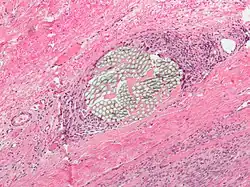

- Tissue reactivity: inflammatory response of the surrounding tissue that can cause materials to break down quicker and lose tensile strength. Non absorbable synthetic suture have the lowest of tissue reactivity, while the absorbable natural fibers have the highest rates of tissue reactivity.[4]